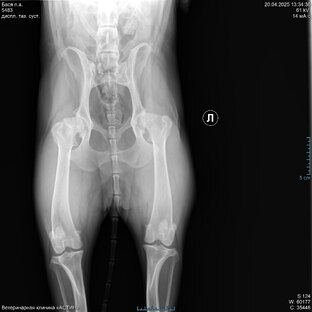

Протезирование ТБС (тазобедренного сустава) собаке. Часть 3

Протезирование ТБС (тазобедренного сустава) собаке. Часть 2

Протезирование ТБС (тазобедренного сустава) собаке. Часть 1